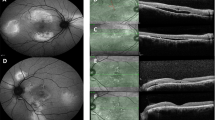

The smoking history, course of disease findings, and visual function of all patients are summarized in the supplementary data (Table S1). The mean BCVA improved significantly from 0.13ā±ā0.24 logMAR units at baseline to 0.00ā±ā0.25 logMAR units at the final visit (pā<ā0.001, Wilcoxon rank sum test). Twenty-two patients (48.9%, all male) were current smokers at the time of the initial examination and had a mean BI of 525.5. Seven patients (15.6%, 6 males and 1 female) were former smokers, all of whom had quit smoking more than five years earlier, with a mean Brinkmann index of 402.9. The remaining 16 patients (35.6%, 6 male and 10 female) had never smoked. The mean age of the current smokers was 48.0ā±ā9.0 years, and that of the current nonsmokers (formerā+ānever) was 49.1ā±ā11.6 years, with no significant differences (pā=ā0.570, MannāWhitney U test). Of the 22 current smokers, 16 stopped smoking cigarettes completely, and 6 reduced their number of cigarettes smoked from 10 or more per day to 1ā2 per day after the smoking cessation instructions were provided. Due in part to the explanation of the risks of smoking and the possible benefits of lutein supplements to the patient and his/her family, and in part to the collaboration with the smoking cessation physician, there were no dropouts among the chronic CSCR patients picked up in the study. The mean CCT of all patients was 395.1ā±ā133.9 μm at the first visit and 357.1ā±ā129.4 μm at the final examination. The decrease was significant (pā<ā0.001, Wilcoxon rank sum test). The mean SRD of current smokers decreased significantly from 138.4ā±ā123.6 μm to 2.81ā±ā14.6 μm, and that of nonsmokers decreased from 143.2ā±ā98.3 μm to 7.48ā±ā20.7 μm (pā<ā0.001 for each, Wilcoxon rank sum test; Fig.Ā 1A, B). The mean CCT of current smokers decreased significantly from 420.1ā±ā142.6 μm to 372.6ā±ā141.2 μm, and that of nonsmokers decreased from 368.0ā±ā120.8 μm to 340.3ā±ā115.8 μm (pā=ā0.0002 and pā=ā0.0131, respectively, Wilcoxon rank sum test, Fig.Ā 1C, D). The CCT increased in 8 eyes (14.8%), including 3 PC-treated eyes and 2 persistent CSCR eyes.

Changes in serous retinal detachment (SRD) height and central choroidal thickness (CCT) in smokers and nonsmokers with chronic CSCR. Compared with the initial visit and the final visit, the mean SRD for both current smokers (A) and nonsmokers (B) was significantly lower, and the mean CCT for both current smokers (C) and nonsmokers (D) was also significantly lower (Wilcoxon rank sum test for all).